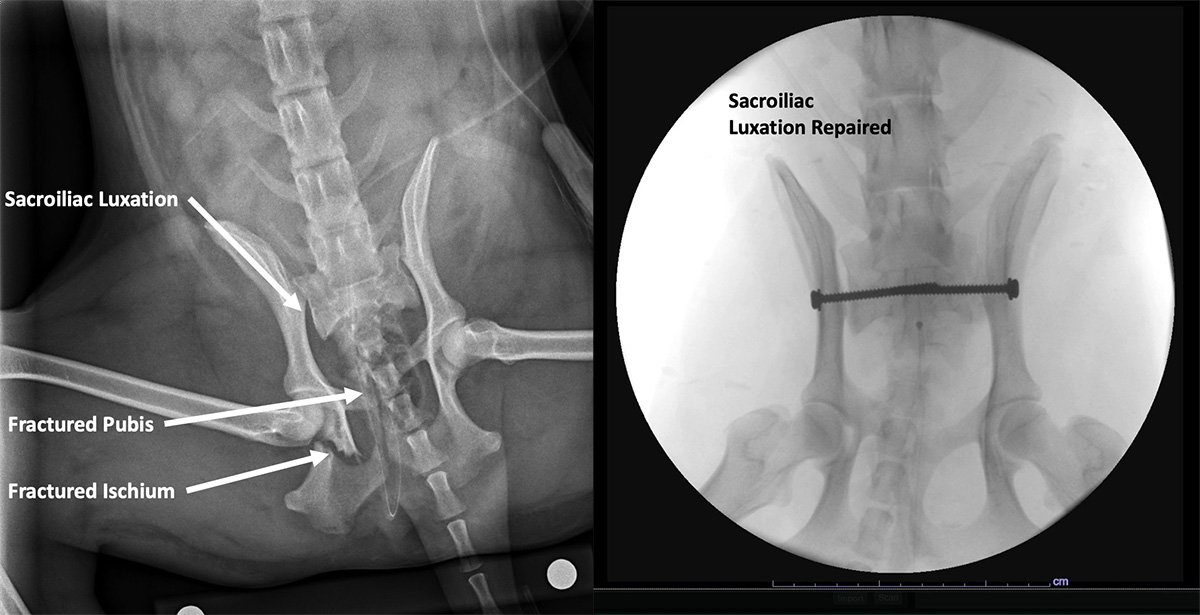

From www.k9orthosurgeon.com

Sacroiliac Luxation Repair Arizona Canine Orthopedics & Sports Medicine Si Joint Fracture X Ray It has little movement and its main function is to. — proper collimation: — sacroiliac (si) dislocations and crescent fractures include a spectrum of injuries involving the pelvis which can lead to instability and pelvic. Most cases of si joint injury respond to conservative management, including. Sacroiliac (si) joints and the first two segments of sacrum must be. Si Joint Fracture X Ray.